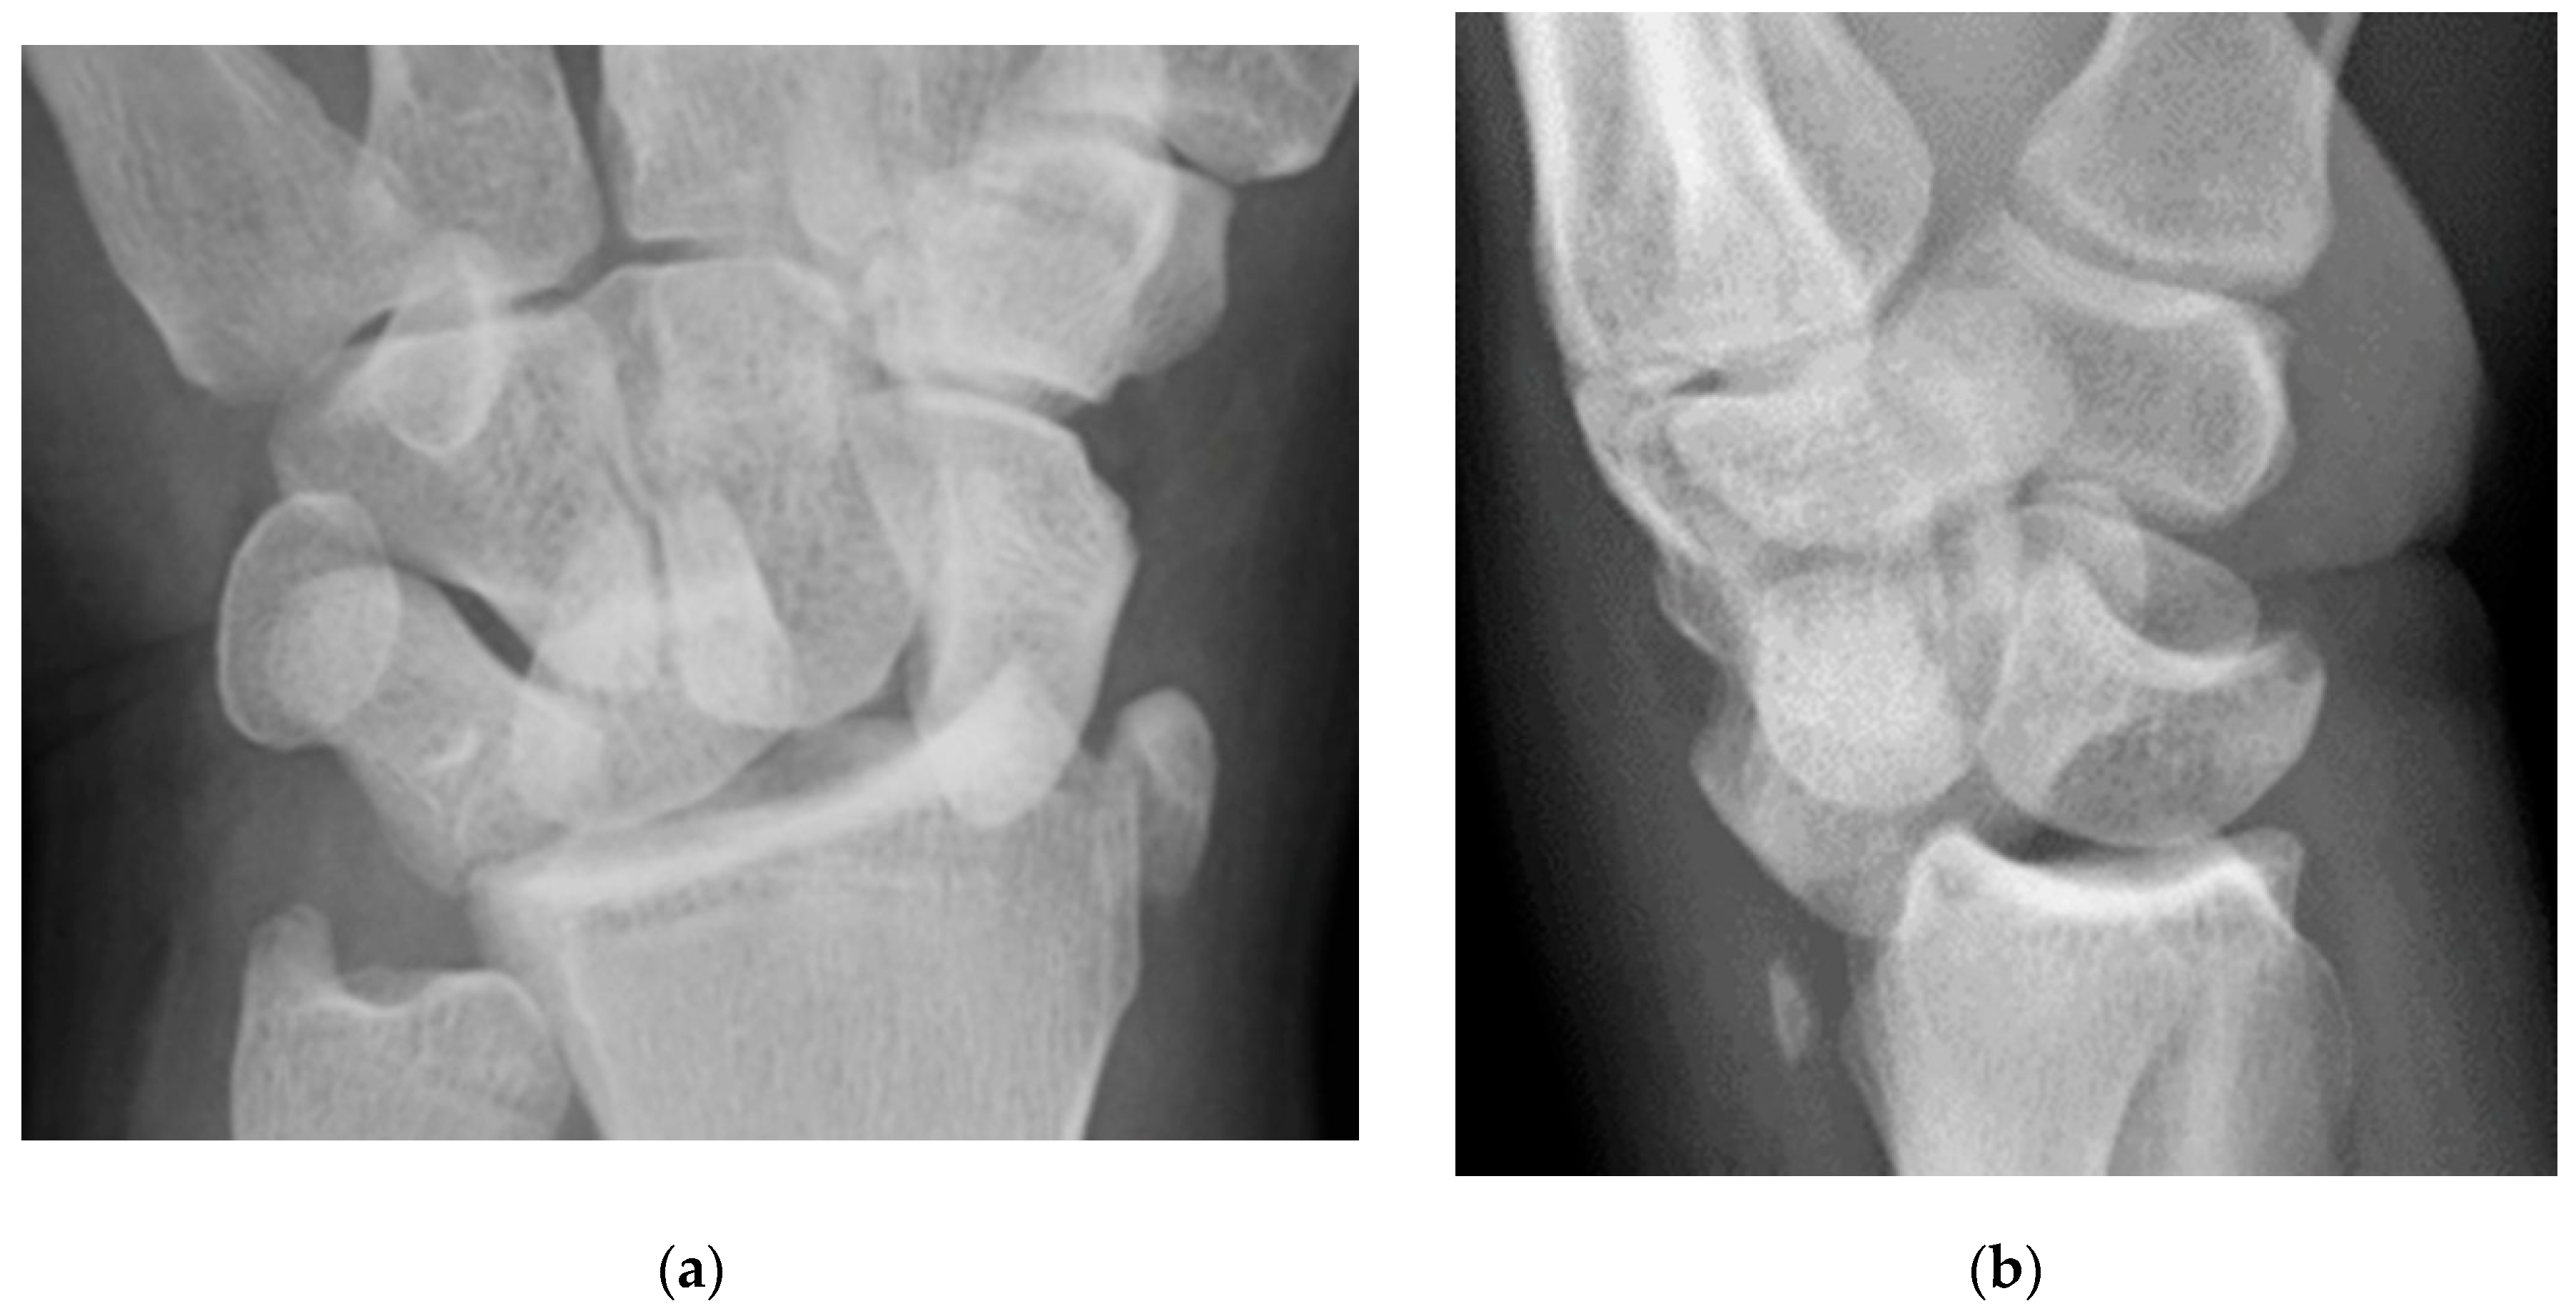

Figure 4. (a) Lateral radiograph of the wrist showing Humpback deformity (arrow) after a scaphoid fracture. (b) Sagittal CT reformation of the wrist showing the full extent of a humpback deformity with dorsal prominence at the site of the scaphoid fracture (arrowheads); image courtesy of Frank Gaillard, Radiopaedia.org, rID: 18269.

The majority of scaphoid fractures (70%) occur through the waist of the scaphoid, with 10% of scaphoid fractures involving the distal third, and 20% involving the proximal third (Figure 2 and Figure 3) [2,14]. With a scaphoid waist fracture, dorsal prominence at the fracture site due to dorsal angulation is known as humpback deformity (Figure 4). This deformity is important to recognize, as it needs to be more aggressively managed due to high risk of nonunion [15]. Additionally, if the two fragments unite with a humpback deformity, it may further destabilize the wrist. This humpback deformity may also be associated with dorsal intercalated segment instability (DISI), which will be covered in more detail later.